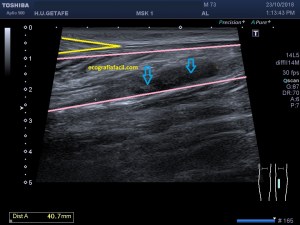

Con la eco pasa igual…cuando queremos estudiar, por ejemplo, el recto anterior del muslo en axial,perfecto…pero en longitudinal, como la imagen 2, se complica porque desde la rótula a la inserción en la cadera, tenemos mucho recorrido. En este caso hacemos lo mismo que cuando hacemos la foto del atardecer…nos ponemos en un extremo, activamos la funciona, recorremos suave y continuamente por la anatomía que queremos fotografiar y ya está…mira la pantalla y no el movimiento de tu mano,como si hicieses la foto, ves la pantalla,pero no como mueves el teléfono.

Es muy útil para lesiones que han crecido mucho y no podemos conjugar en una sola imagen, por ejemplo, un lipoma, cuando superan la medida de la huella de la sonda no son medibles, hay que usar «panoramic view», y como este caso, otros muchos.

En la imagen 3 ves una imagen de un lipoma, mide 7 cms, la huella de la sonda mide 5cms, la «panoramic view» posee una regla centimetrada que sigue el contorno de la imagen, justo en la profundidad de la misma y lo marca la flecha amarilla. La profundidad la marca la flecha roja y la flecha blanca marca el rango centimetral de los 5cms, fíjate que la línea blanca es ligeramente mayor cada 5 cms. Sirve de referencia, como en la imagen 4 donde ves una colección en el glúteo de más de 10 cms.